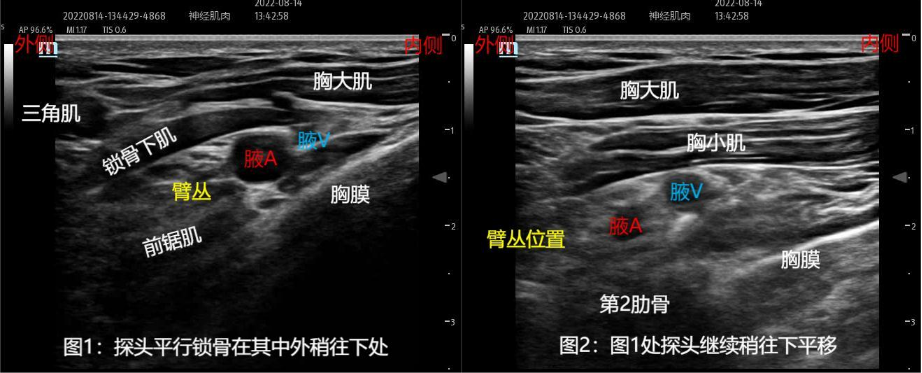

上图为探头扫查时加压的图像:静脉被压瘪,此处重点是刚开始扫查时先显示锁骨下肌,探头稍往下后,锁骨下肌消失,胸大肌下方就出现了胸小肌图像(胸小肌比较水平)。同时注意,胸小肌的中部一般是“肋锁间隙臂丛”在下方的终点。